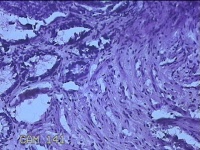

性别

男

年龄

40岁

临床诊断

混合痔

一般病史

反复肛门肿物突出15年。

标本名称

肛门肿物

大体所见

灰白暗红色肿物0.7x0.5x0.2cm一个,表面糜烂。

脱水、透明,浸蜡、脱蜡效果不佳,制片质量差。